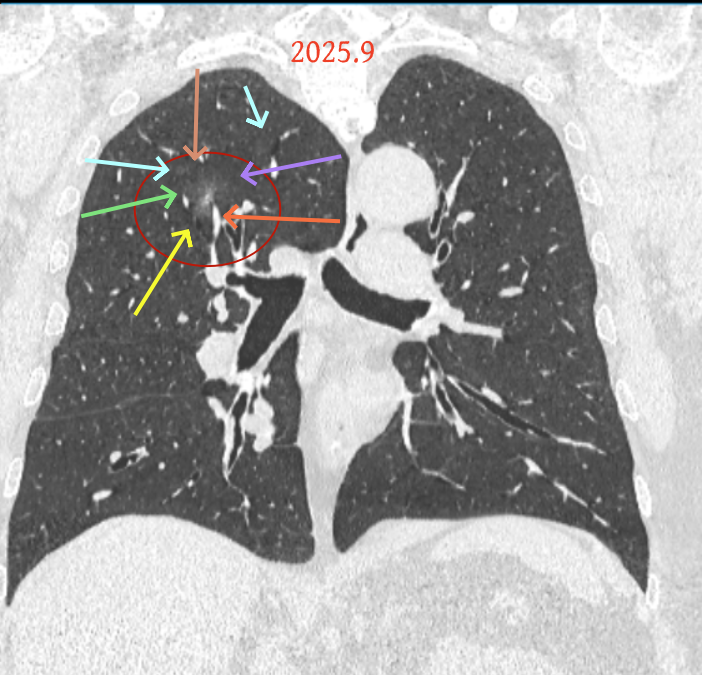

方形的是25年的,红色的主病灶,磨玻璃密度伴少许略偏高点密度,但还说不上典型混合磨玻璃病灶,考虑原位癌或微浸润性腺癌可能性大;蓝色的轮廓与边界欠清,位置靠上叶中央,无法段切或楔切;黄色的多发均淡而纯,分布在两肺。圆形粉色的是主要的两处23年时的样子,对比说不上很明显进展。鉴于若手术得切肺叶,何况两肺他处仍的结节,年纪又74了。我倾向保守点,先6-9个月复查,等进展并风险增加再来考虑怎么办的事。意见供参考!

病灶B似乎灶内有少许密度略偏高,但瘤肺边界欠清晰,总体说不上太显著的进展。

当时结友自己还觉得有点实性成分,血管感觉也有增粗。而我觉得整体密度仍是磨玻璃,轻微的变化仍不足以影响临床决策的程度。